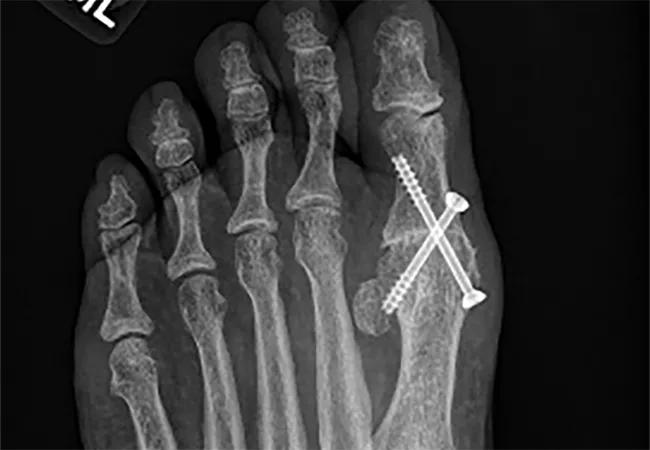

Figure 2. Anterior-to-posterior radiograph three years after left fusion and one year after right fusion.

A healthy 52-year-old fitness instructor presented with bilateral hallux rigidus (Figure 1). She initially underwent arthrodesis of the left great toe. Two years later, the contralateral fusion was elected. Now she is at full unrestricted physical activity and pain-free with bilateral first MTP joint fusions (Figures 2-4).

Overall, patients do well after first MTP joint fusion and are happy with their results, as demonstrated in these two cases.